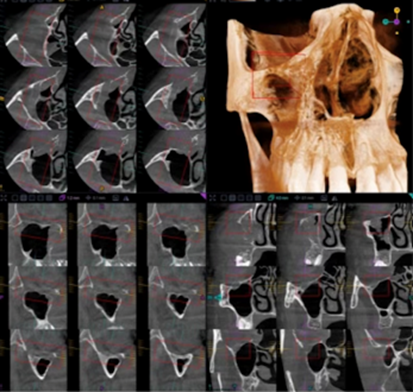

More specifically, these observations indicated a mass on the posterior-superior aspect that extended into the right infraorbital canal (Figure 5). Discontinuities were observed along the medial inferior walls of the anterior aspects of the canal. Moreover, the superior wall of the canal appeared elevated and thinned but not fully discernible radiographically. The overall diameter of the right infraorbital canal appeared abnormally enlarged, indicating possibility of perineural spread. These radiographic findings were suggestive of malignancy involving the right maxilla. Medical referral was indicated for further evaluation and management.

Figure 5: Cone beam computed tomography demonstrating suspected extension of the lesion into the right infraorbital canal.

The radiographic presentation necessitated consideration of several malignant processes in the differential diagnosis. Osteosarcoma was initially contemplated due to its potential for aggressive maxillofacial bone destruction; however, typical radiographic characteristics, such as mixed radiopaque-radiolucent appearances, osteoid matrix deposition, and prominent sunburst periosteal reactions were absent. Instead, the lesion demonstrated diffuse periodontal ligament widening, permeative osteolysis, cortical perforation, and extensive soft tissue extension, features more consistent with lymphoproliferative malignancies. The lack of mineralized matrix production further diminished the likelihood of osteosarcoma. Moreover, the unexplained enlargement of the infraorbital canal suggested possible perineural involvement, a finding that can accompany aggressive lymphomas. Collectively, the radiographic and clinical characteristics favored a diagnosis of a high-grade B-cell lymphoma, prompting an incisional biopsy to obtain definitive histopathological confirmation.